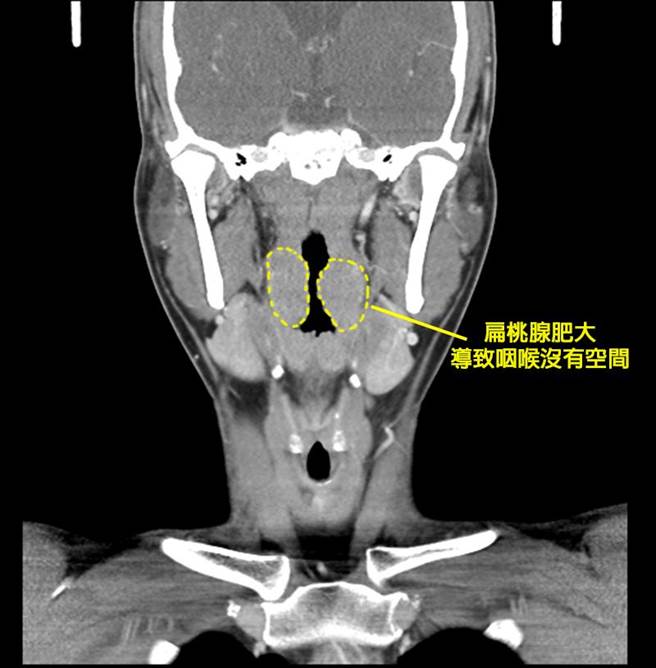

澄清医院耳鼻喉科主任徐毓婷指出,经检查这名阿兵哥两侧扁桃腺几乎kiss在一起。(澄清医院提供/冯惠宜台中传真)

徐毓婷表示,经检查发现该患者的双侧扁桃腺肥大程度已是第4期,左右的扁桃腺已kiss在一起,晚上睡觉时因肌肉松弛,氧气在嘴巴里和扁桃腺空间振动,就会产生打鼾声。由于白天很专注用鼻子呼吸,因此不会感觉有什么异状。